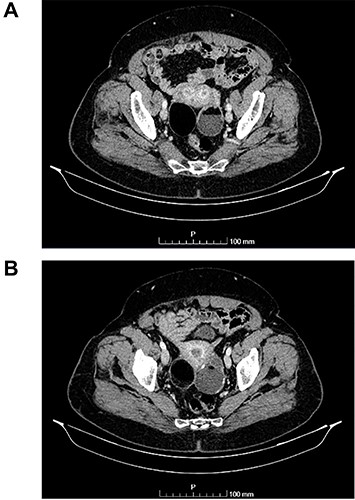

(A and B) Sagittal images of CT showing bilateral ovarian lesions.

The authors report the case of an asymptomatic 76-year-old female patient, referred to our Gynaecologic Clinic, due to suspicious adnexal lesions on a pelvic ultrasound (US). Menopause occurred at age 53. She had no history of abnormal uterine haemorrhage. Her menstrual cycles had been regular. She had had three gestations: two late abortions and one normal delivery, after which she breastfed. At our clinic, upon examination, vulva, vagina and cervix had no apparent lesions. The vaginal US revealed a right adnexal avascular cystic lesion of 65 mm, a left adnexal hyperechogenic cystic lesion of 60 mm, a normal sized uterus, a diffusely heterogeneous myometrium, an endometrial thickness of 8 mm and heterogenous intracavitary liquid. Her risk of ovarian malignancy assessment (ROMA) score was 28.1%, for a cut-off of 25.3%. Cancer antigen (CA) 125 and Human epididymis protein 4 (HE4) were 25.9 and 98.2, respectively. Lactate dehydrogenase (LDH), alpha fetoprotein (AFP) and beta human chorionic gonadotropin (bHCG) were normal. She subsequently had a magnetic resonance (MR) done (Fig. 1), which suggested bilateral ovarian teratoma. She also had an upper digestive endoscopy and a hysteroscopy that were normal and a computed tomography (CT) done (Figs 2–4) that showed: in the right adnexal region, a solid well-demarcated tumoural mass of 55 mm, with predominantly fat density, peripherical calcifications and a central hyperdense image (similar to a tooth), suggestive of a teratoma; in the left adnexal region, a predominantly cystic bilobated tumoural mass of 65 mm, with peripherical calcifications and an area of fat density, also suggestive of teratoma; and no additional disease. This case was presented at our Multidisciplinary Tumour Board, where surgery was proposed. Thus, she underwent exploratory laparotomy, peritoneal washing, total hysterectomy and bilateral adnexectomy, which ran uneventfully. Intra-operative frozen section excluded ovarian malignancy. She had an uneventful recovery and was discharged home on the third post-operative day. The pathological report revealed bilateral mature cystic teratoma with representation of the three germinative layers and thyroid parenchymal tissue (struma ovarii) (Fig. 5). Both ovaries were atrophic and had a cavitated lesion covered by respiratory epithelium with hyaline cartilaginous, adipose, smooth muscular and mucosa-associated lymphoid tissues (positivity for CD3 and CD20), seromucinous glands and thyroid follicles (homogenous positivity for thyroglobulin). Thyroid follicles were well differentiated, without features of malignancy. Fallopian tubes were normal. There were also uterine leiomyomas and a mucosal endocervical polyp. She was euthyroid and had a thyroid US done, which was normal. Follow-up at first post-operative month, remaining asymptomatic.